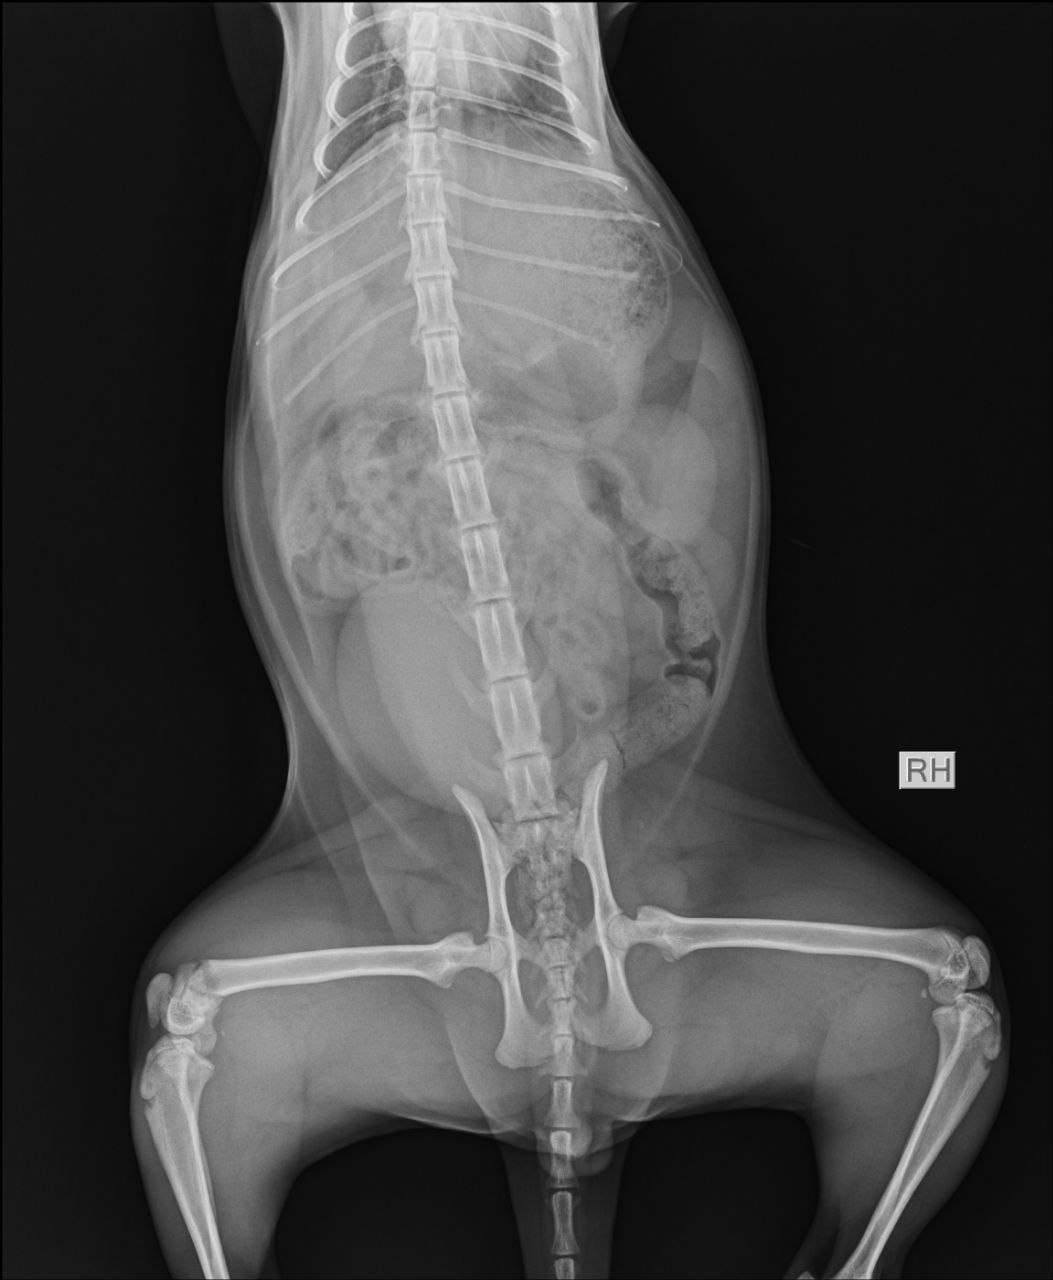

Перелом бедренной кости, требуется операция. В остальном здоров и бодр, ест, пьёт, ходит в туалет.

Тут закрытый перелом не кости а коленного сустава, сильно выраженная бронхиальная картина. Антибиотик нужен

Он писает? На снимке мочевой как дыня переполнен